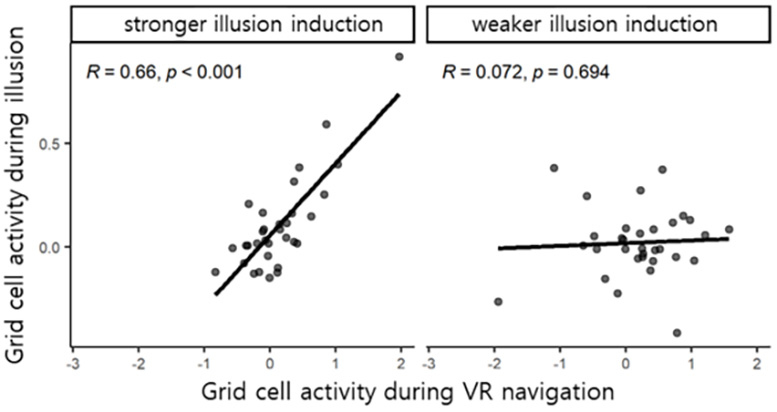

דמיון בין פעילות תאי רשת הנגרמת באשליה ו-VR הניווט. קרדיט: מכון קוריאה למדע וטכנולוגיה

ד"ר מון הצהיר, "בניגוד למחקרים קודמים של תאי רשת אנושיים, אשר הסתמכו על שינויים ברמזים סביבתיים חזותיים מנקודת מבט של גוף ראשון, הצענו לאחרונה אלמנט מחקרי מרכזי של שילוב אותות גופניים רב-חושיים." והוסיפו, "אנו מתכננים לבצע המשך מחקר שיתופי בינלאומי כדי להבין יותר את מנגנוני המוח העומדים בבסיס האשליות הנגרמות על ידי מחלות נפשיות ונוירולוגיות שונות, ולפתח טיפולי גירוי מוחי לא פולשניים שיכולים להקל על תסמינים אלו".